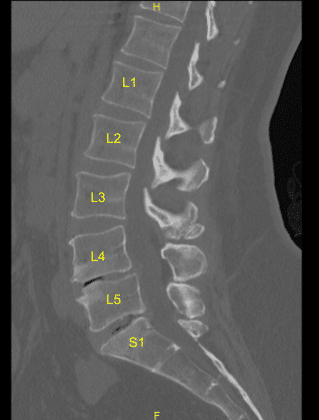

The imaging showed malfunction and suboptimal placement of the right sacral pedicle screw. Surgery was recommended to decompress the lumbar nerve root being impinged by the pedicle screw and stabilize the lumbar spine.

Intraoperative CT scan was obtained, and data was transferred to the neuronavigation computer and accuracy was verified. Neuronavigation techniques were used to cannulate the right-sided first sacral segment which was then palpated for breaches and measured at the depth of 35 mm. A 6.0 mm navigated tap was used to thread the cannulation. It was again palpated for breaches and a 7.5 x 35 mm titanium pedicle screw was placed with good bony purchase and tightness.

Next, the patient was re draped and a second intraoperative CT scan was obtained showing correct positioning of this pedicle screw. Neuromonitoring signals were stable throughout. Next, the L5-S1 transverse process and ala were decorticated with a high-speed drill for the arthrodesis after exploring the fusion and failing to identify bony arthrodesis and bone graft.